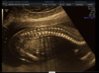

Na zdjęciach profil, kręgosłup, pupa, stopa, serce :-)